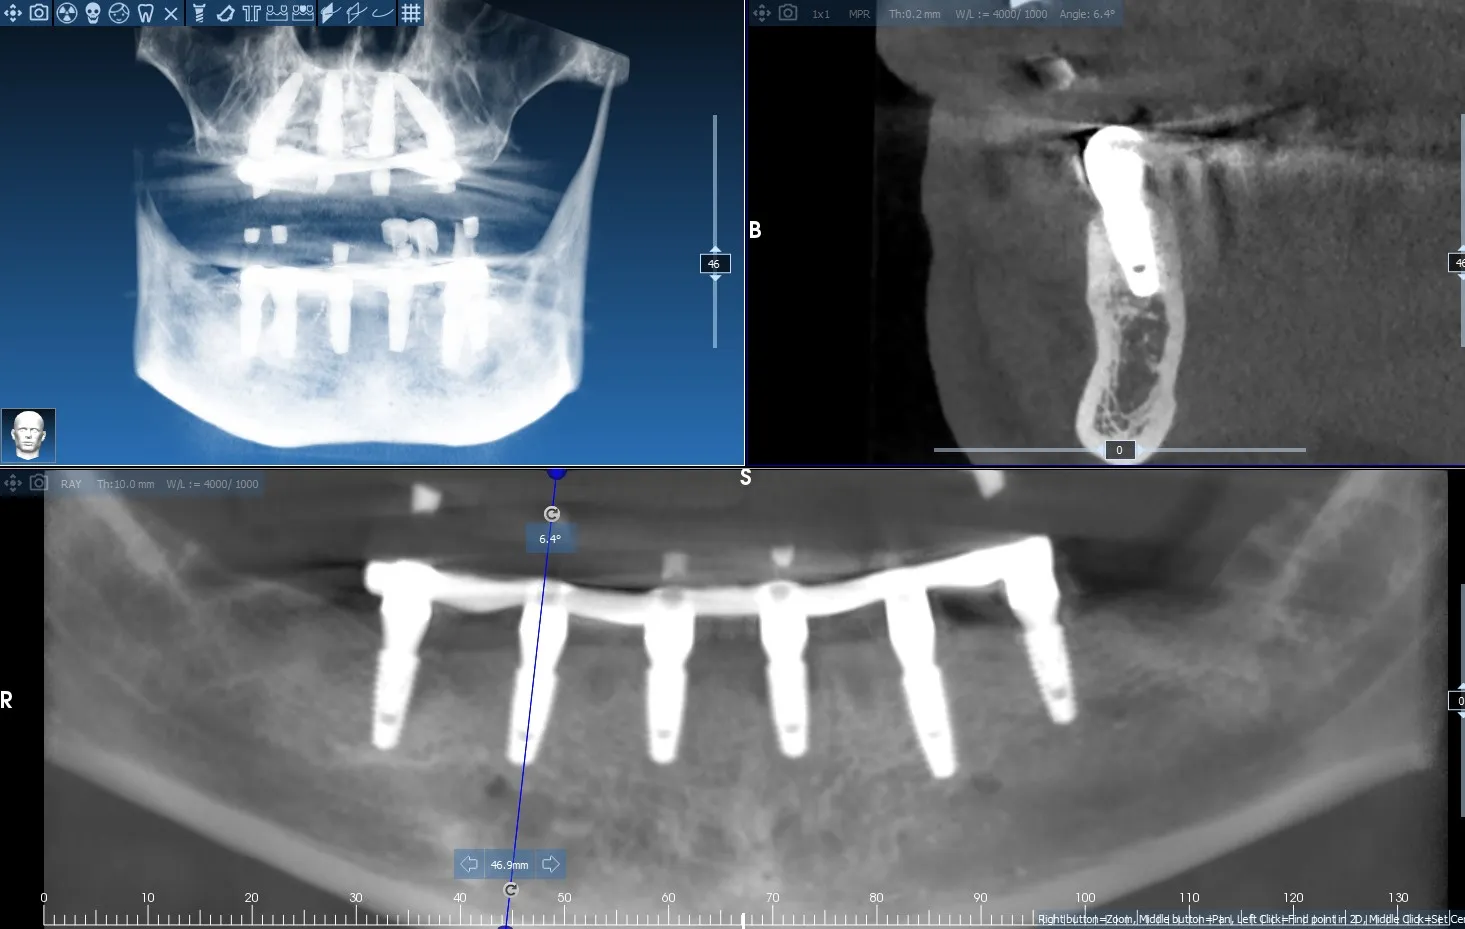

Dual Arch Rehabilitation — All-on-4 & All-on-6

Complete upper and lower jaw rehabilitation. All-on-4 concept for maxilla and All-on-6 for mandible with custom surgical guides.